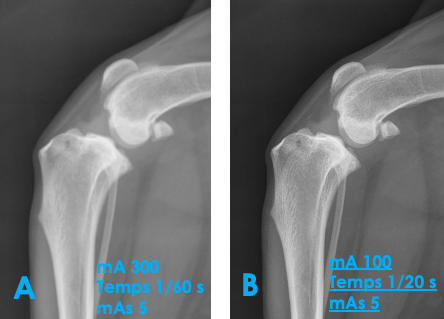

Qu’est-ce qui explique la différence de qualité entre ces 2 images?

A) la radio B a été effectuée avec un mAs plus élevé pour le même kVp

B) la radio B a été effectuée avec un plus petit filament

C) la cassette était plus loin du membre pour la radio B

D) l’animal a bougé lors de la radio A

C)